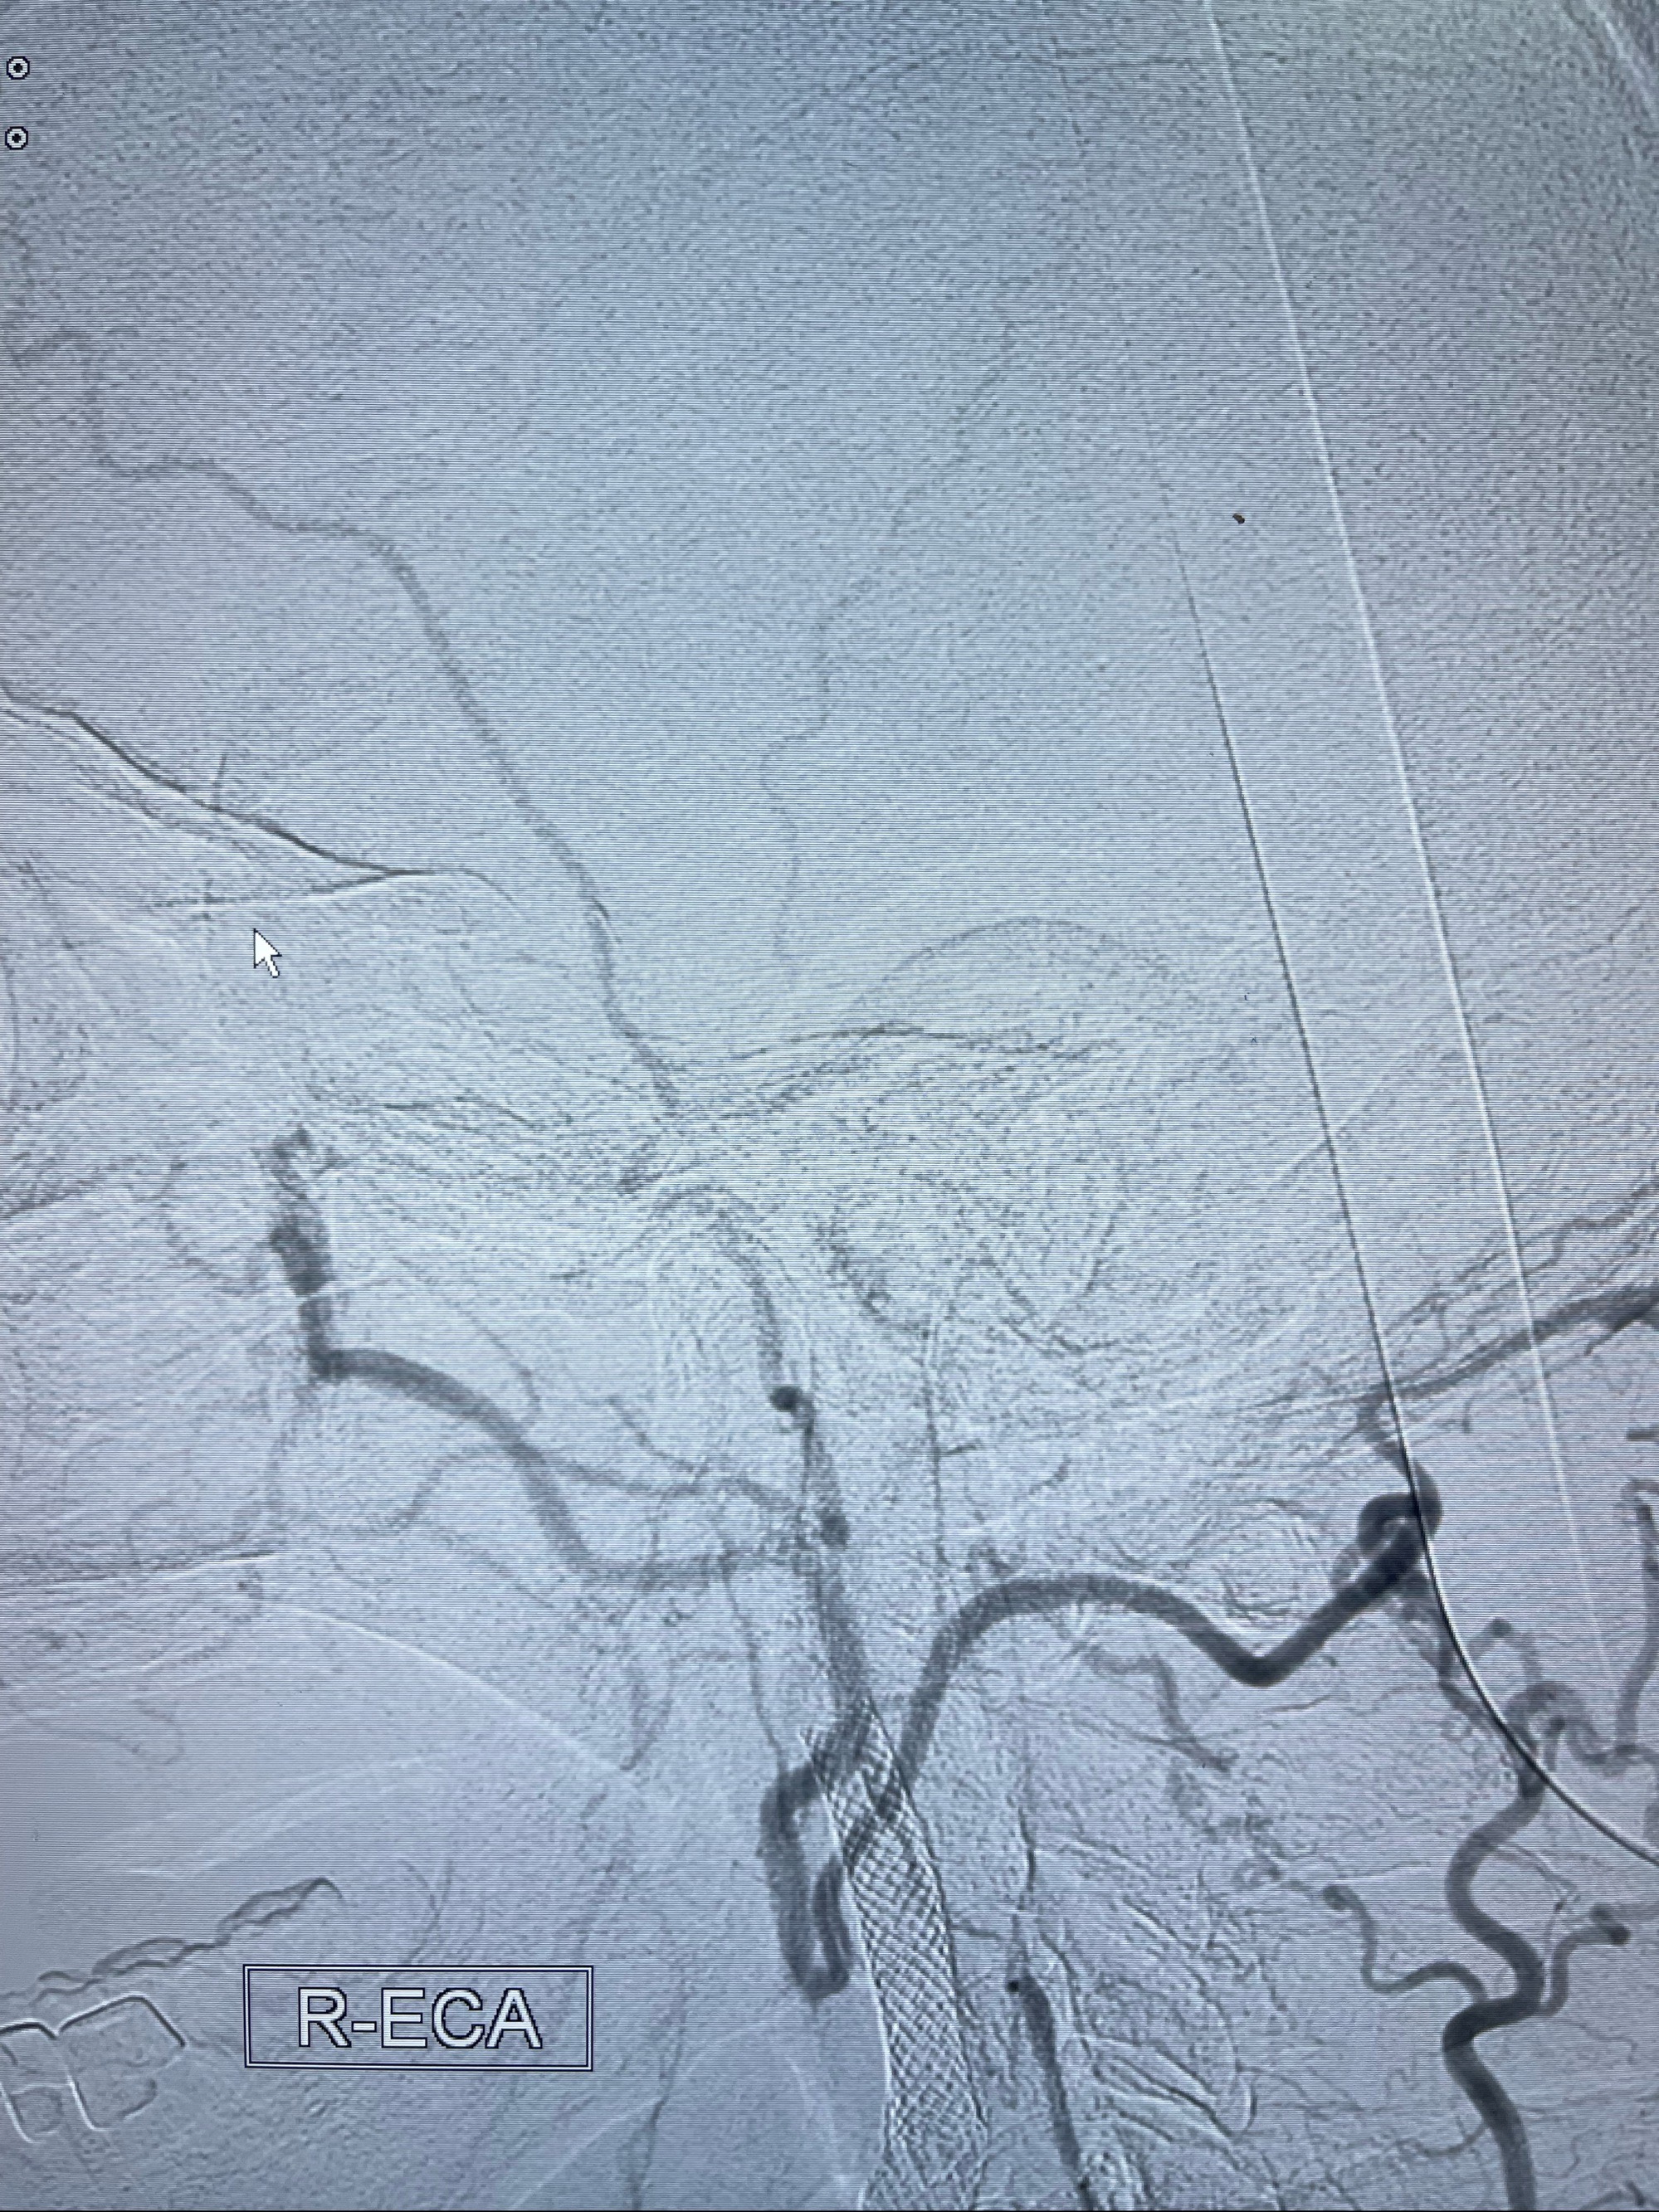

2023-07-10DSA:右侧颈内动脉岩骨段夹层伴中偏重度狭窄改变,左侧颈总动脉闭塞、右侧颈外动脉由右侧肋颈干甲颈干吻合代偿

左侧颈总动脉起始段至分叉部闭塞,起始部呈现子弹头样改变

左侧椎动脉可见代偿显示左侧前循环

经导引导管造影显示支架远端颈内动脉不规则狭窄伴局部充盈缺损,同时行全身肝素化5ml

泄除球囊造影显示局部管腔扩张佳

即刻造影显示狭窄扩张佳

即刻造影显示支架贴壁佳